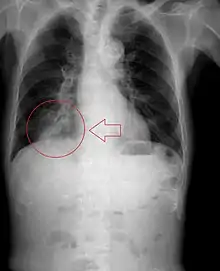

Pulmonary aspiration is the entry of material such as pharyngeal secretions, food or drink, or stomach contents from the oropharynx or gastrointestinal tract, into the larynx (voice box) and lower respiratory tract, the portions of the respiratory system from the trachea (windpipe) to the lungs. A person may inhale the material, or it may be delivered into the tracheobronchial tree during positive pressure ventilation. When pulmonary aspiration occurs during eating and drinking, the aspirated material is often colloquially referred to as "going down the wrong pipe".

Consequences of pulmonary aspiration range from no injury at all, to chemical pneumonitis or pneumonia, to death within minutes from asphyxiation. These consequences depend on the volume, chemical composition, particle size, and presence of infectious agents in the aspirated material, and on the underlying health status of the person.

In healthy people, aspiration of small quantities of material is common and rarely results in disease or injury. People with significant underlying disease or injury are at greater risk for developing respiratory complications following pulmonary aspiration, especially hospitalized patients, because of certain factors such as depressed level of consciousness and impaired airway defenses (gag reflex and respiratory tract antimicrobial defense system). The lumen of the right main bronchus is more vertical and slightly wider than that of the left, so aspirated material is more likely to end up in this bronchus or one of its subsequent bifurcations.